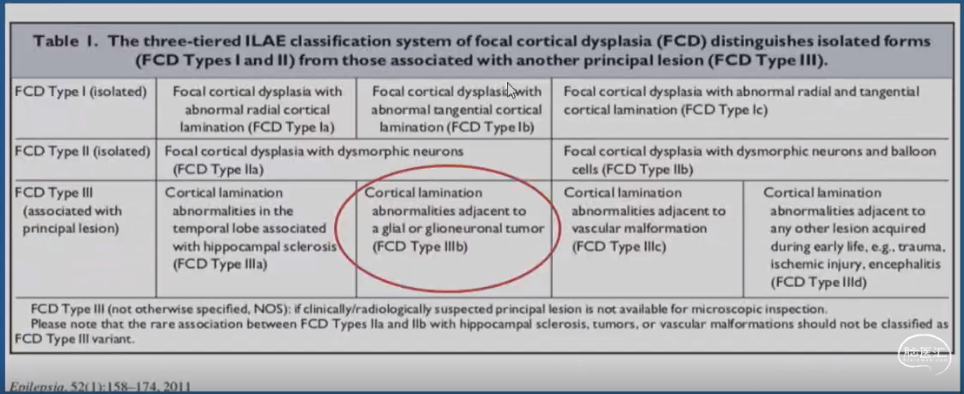

结构性病因诊断

•局灶性皮质发育不良(FCD)Ⅲb型